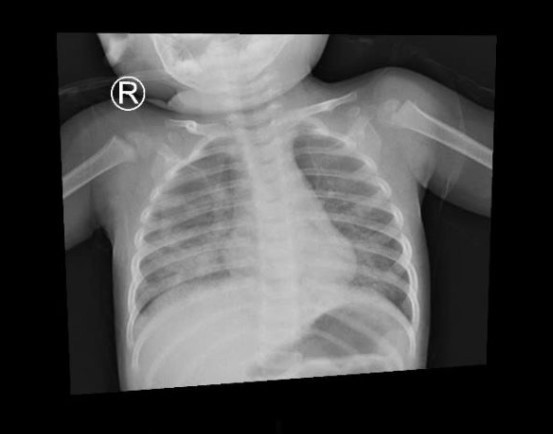

| Hình ảnh X quang ngực lúc nhập viện cho thấy tình tổn thương phổi lan tỏa 2 phế trường bên phải nhiều hơn bên trái, gây suy hô hấp nặng. |